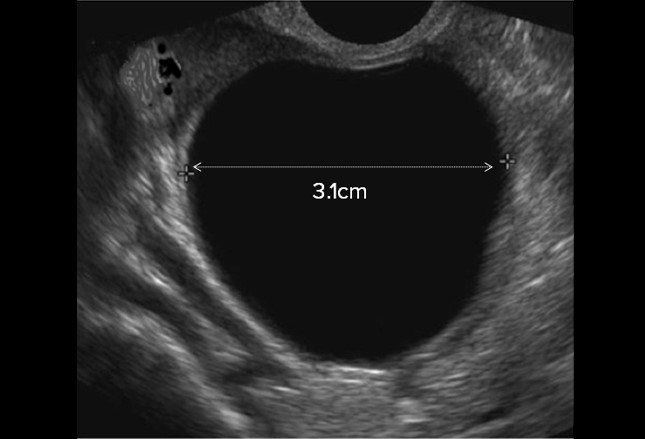

- Transvaginal Scan

- The scan provides detailed images which help to determine if the pelvic organs are normal or have abnormalities such as:

- Ovarian cysts